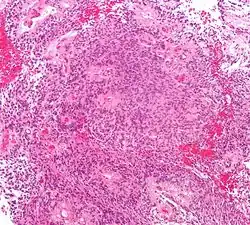

- Основным гистологическим типом является истинная эпендимома , для которой типично наличие периваскулярных и истинных «розеток». Периваскулярные «розетки» («псевдорозетки», «лучистая корона») состоят из клеток новообразования, которые располагаются вокруг кровеносных сосудов. В истинных «розетках» опухолевые клетки находятся вокруг каналов, которые выстланы эпендимарными клетками.

Папиллярная эпендимома